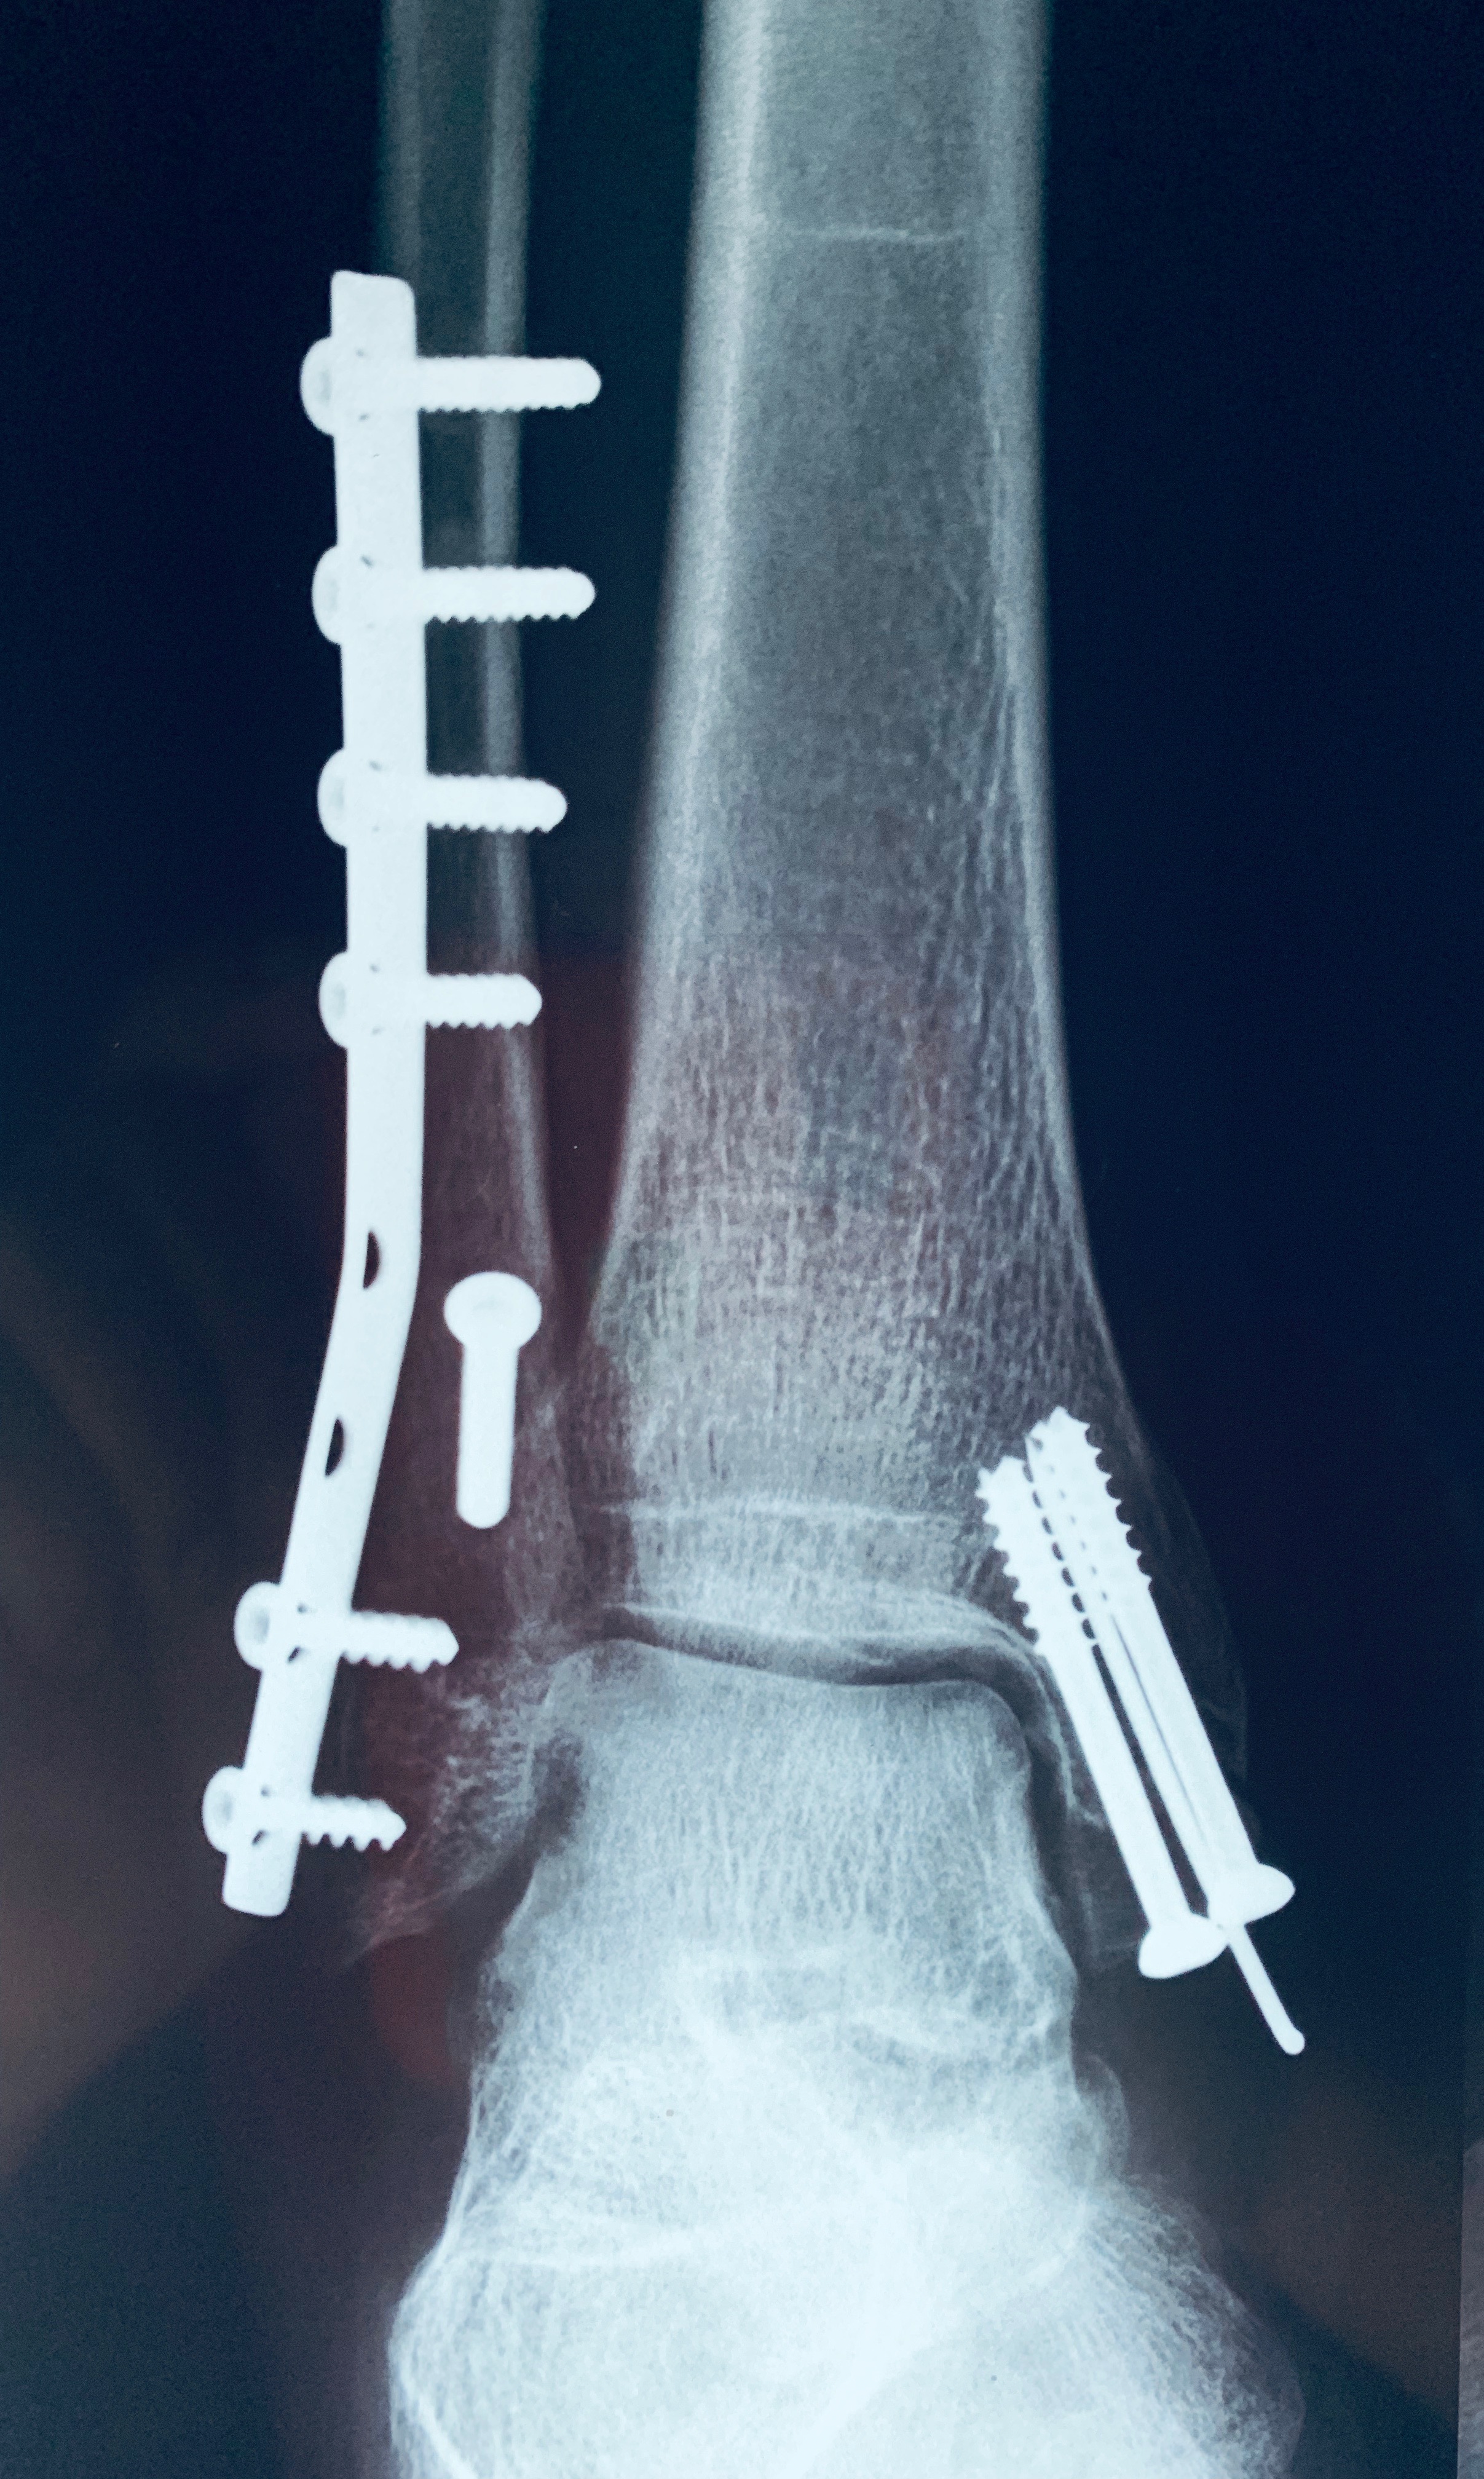

ORIF with Tubular Plating-Lag Screws

A 29 year old male case of post-traumatic left-sided Pott’s fracture was treated.

Surgery performed was open reduction & internal fixation with 1/3rd tubular plate with lag screws.